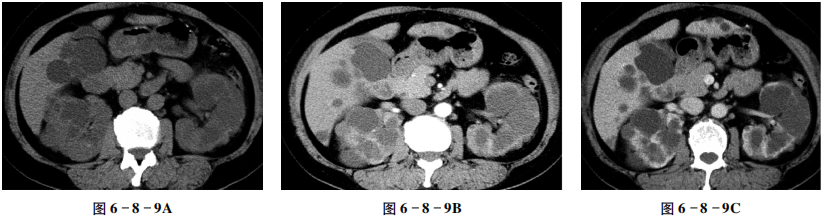

【CT征象】

平扫示双肾,体积增大,边缘不规则,肾内见弥漫性大小不等的囊状低密度区,部分为高密度,部分囊壁见点状钙化,肾皮质变薄(图6-8-9A);增强扫描病变未见明显强化,双侧肾盏、肾盂明显受压(图6-8-9B、C);肝内亦可见多发无强化囊性病变,边缘光滑锐利(图6-8-9D)。

双肾及肝弥漫大小不等囊性病变,边缘光整,无强化。

多囊肾,多囊肝,部分囊壁钙化。

CT表现

①婴儿型:双肾增大,外形保持,肾内布满数毫米大小的囊肿,不伴肾盏、肾盂变形,常合并肝、脾囊肿,少数活到成人者可见门脉高压征象。②成人型:双肾增大,外形呈分叶状,皮髓质内见大小不等的薄壁囊肿,呈蜂窝状,增强扫描囊间肾实质可强化,肾盏、肾盂受压变形,约1/3的病例可合并肝、脾、胰腺囊肿,并常见肾结石。